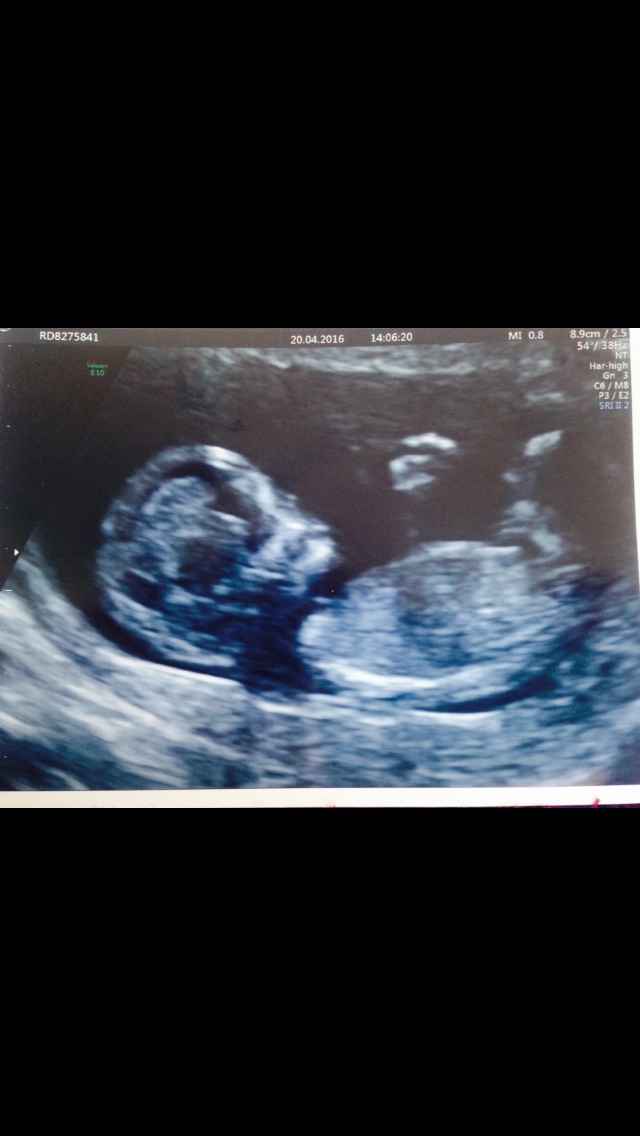

I have a scan on Tuesday and am so nervous as really wants hear pic, it was difficult to see the nub shot in these pics, did anyone else have these feelings, praying for pink

What is gestation on these?? It does look girly but can't sign off without knowing gestation.

Thank you it's 12 weeks 5 days